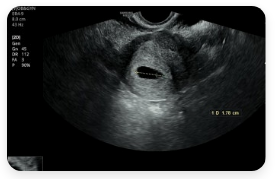

- 생리 지연 후 임신 테스트 양성

- 입덧, 임신 초기 출혈

- 태아 초음파, 정기적인 산전검사